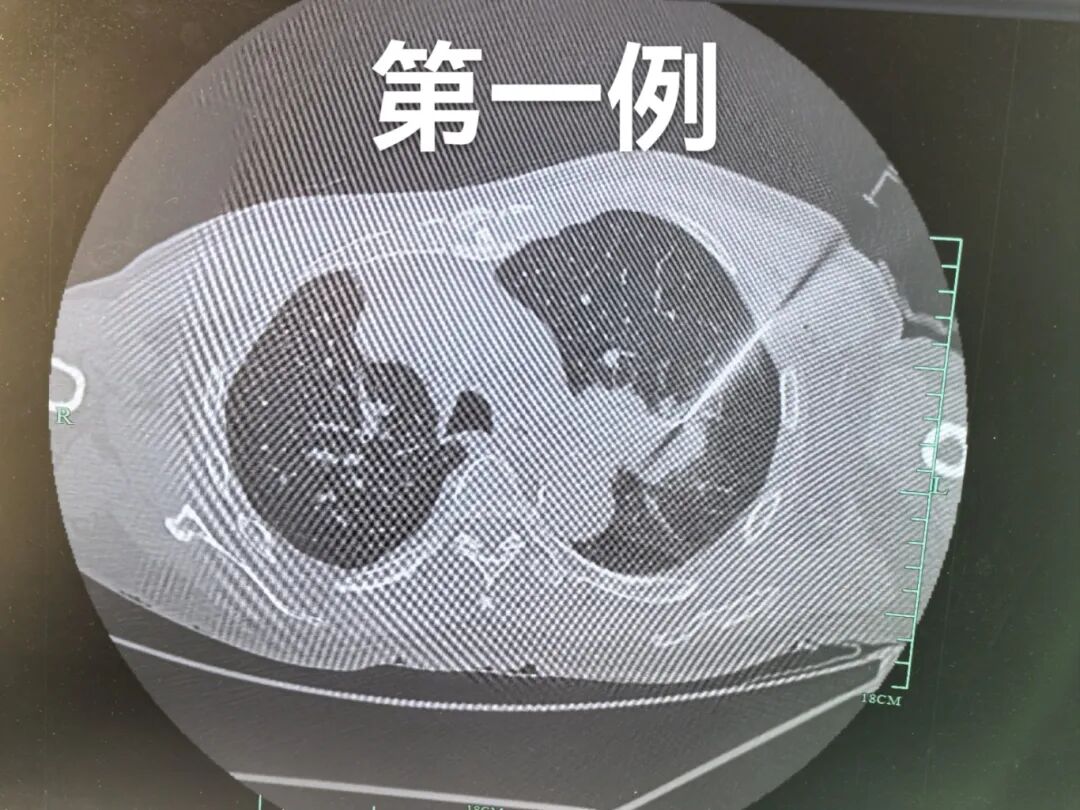

近日,新疆医科大学第四附属医院(自治区中医医院)呼吸一科朱玉龙团队成功实施全疆首例经皮肺穿刺活检联合AI-ROSE人工智能辅助手术现场快速病理诊断术,为三名患者提供了精准的诊断服务。其中,两例患者经过快速现场人工智能诊断与三天后活检组织切片病理诊断相一致,诊断与医院的病理诊断相符。这一成果彰显了AI技术在病理诊断领域的巨大潜力,也为肺癌的早期诊断和治疗提供了新的思路。